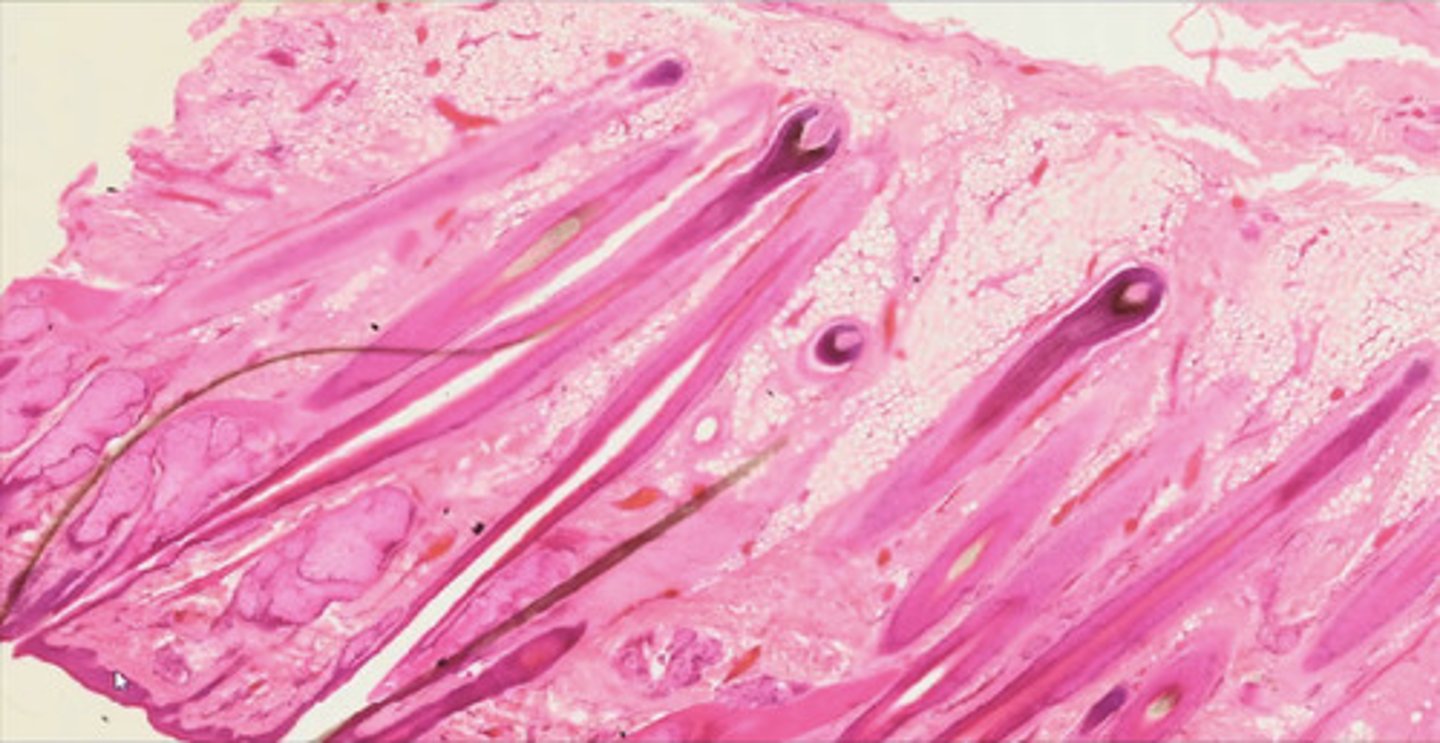

Skóra owłosiona - przekrój podłużny (H+E)